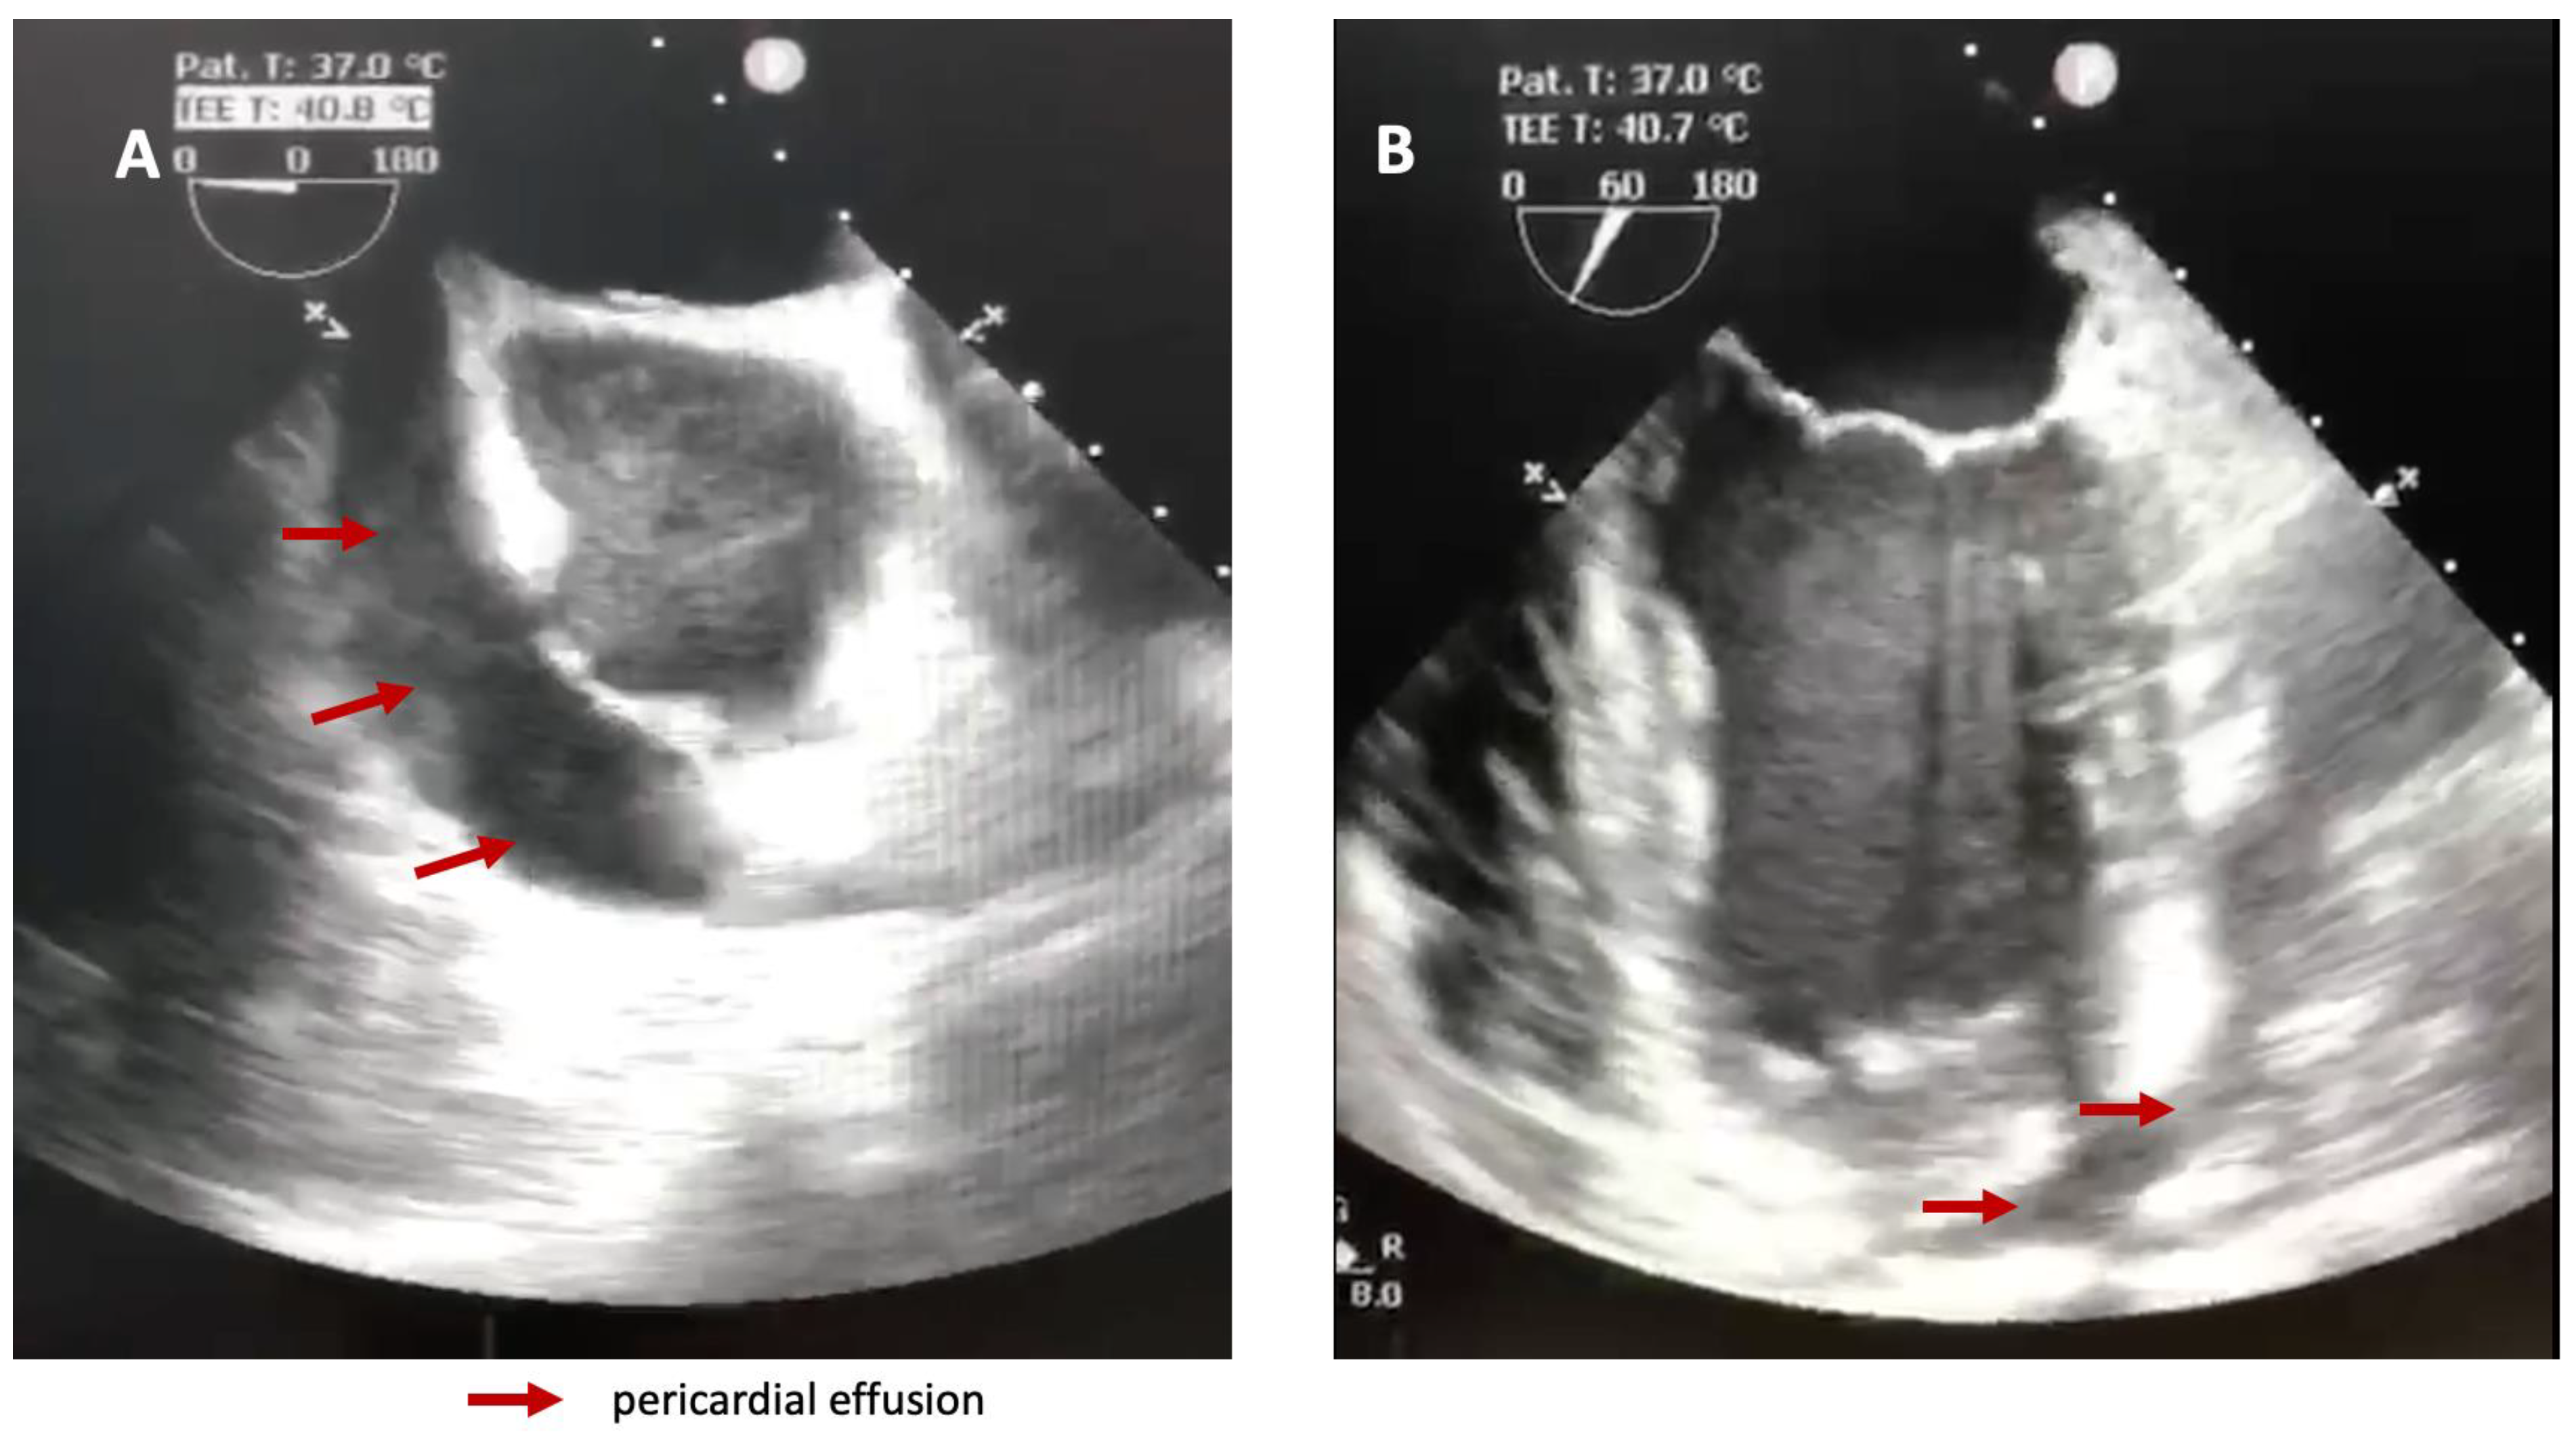

A transesophageal heart ultrasound was promptly performed and confirmed the impressive amount of liquid in the pericardium and right ventricular collapse (Figure 2).

Figure 2. Transesophageal heart ultrasound showing pericardial effusion. A—right atrium and right ventricle, B—Left ventricle.